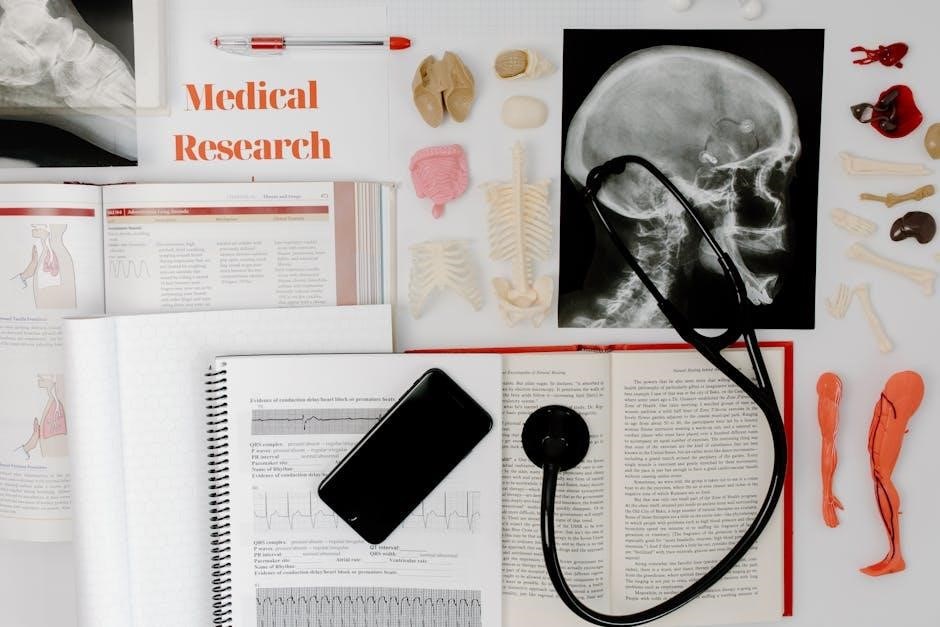

VI. Resources for Studying Anatomy and Physiology

Essential study aids include Nowicki’s Biology, Liachovitzky’s preparatory course, LibreTexts, and interactive tools like the Human Body Explorer and Crash Course videos.

A. Textbooks (Nowicki’s Biology, Liachovitzky’s Preparatory Course)

Core to your studies will be Stephen Nowicki’s Biology textbook, published by Holt McDougal, serving as the primary resource for this course. This comprehensive text provides a solid foundation in biological principles essential for understanding human anatomy and physiology. Complementing this, Liachovitzky’s Human Anatomy and Physiology Preparatory Course (2019) is invaluable.

This preparatory text focuses on familiarizing students with key terminology and fundamental concepts encountered in subsequent, more advanced Anatomy and Physiology I courses. It’s designed to enhance comprehension and build confidence, ensuring a smoother transition into complex topics. Both resources work synergistically, offering a robust learning experience.

B. Online Resources (LibreTexts, Open Educational Resources)

Expanding your learning beyond traditional textbooks, numerous online resources are available. Los Angeles Valley College Library highlights Open Educational Resources (OER) – free, digitally accessible textbooks with Creative Commons licenses, offering royalty-free, academically reviewed content. LibreTexts hosts Liachovitzky’s Human Anatomy and Physiology Preparatory Course, providing a valuable review of basic units.

Hillsborough College’s LibGuides also point to free digital college-level textbooks, ideal for supplemental study. These resources integrate anatomy, physiology, and homeostasis, offering a comprehensive overview. Utilizing OER ensures access to affordable, high-quality materials, supporting your success in mastering the essentials of human anatomy and physiology.

C. Interactive Tools (Human Body Explorer, Crash Course Videos)

Enhance your understanding with dynamic learning tools. The Human Body Explorer provides detailed, 3D interactive images of every body system, allowing for in-depth visualization of anatomical structures and their functions. This immersive experience complements textbook learning, solidifying complex concepts.

Furthermore, the Crash Course video series on anatomy and physiology offers engaging and accessible explanations of key topics. These videos, used alongside resources like Nowicki’s Biology, provide a multi-faceted approach to mastering the essentials. Combining visual exploration with concise video lessons fosters a deeper, more comprehensive grasp of human anatomy and physiology.